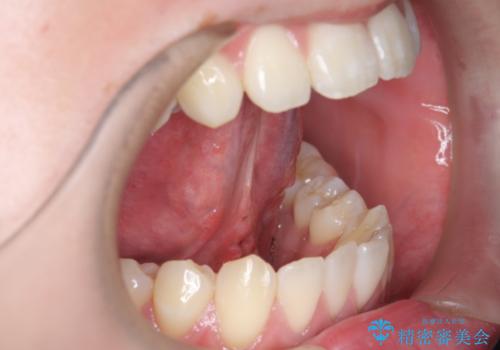

[ 舌小帯の形成 ] 滑舌が悪いと言われる、話しづらい

担当医 大元洋佑

![[ 舌小帯の形成 ] 滑舌が悪いと言われる、話しづらいの症例 治療前](https://seimitsushinbi.jp/wp/wp-content/uploads/2021/07/65efe28f05c8bc8266a054e337d8a987-500x350.jpg?v=1626308574)

![[ 舌小帯の形成 ] 滑舌が悪いと言われる、話しづらいの症例 治療後](https://seimitsushinbi.jp/wp/wp-content/uploads/2021/07/9a0e2d1f2bdecf6d77e84a94c98c2f5e-500x350.jpg?v=1626308612)